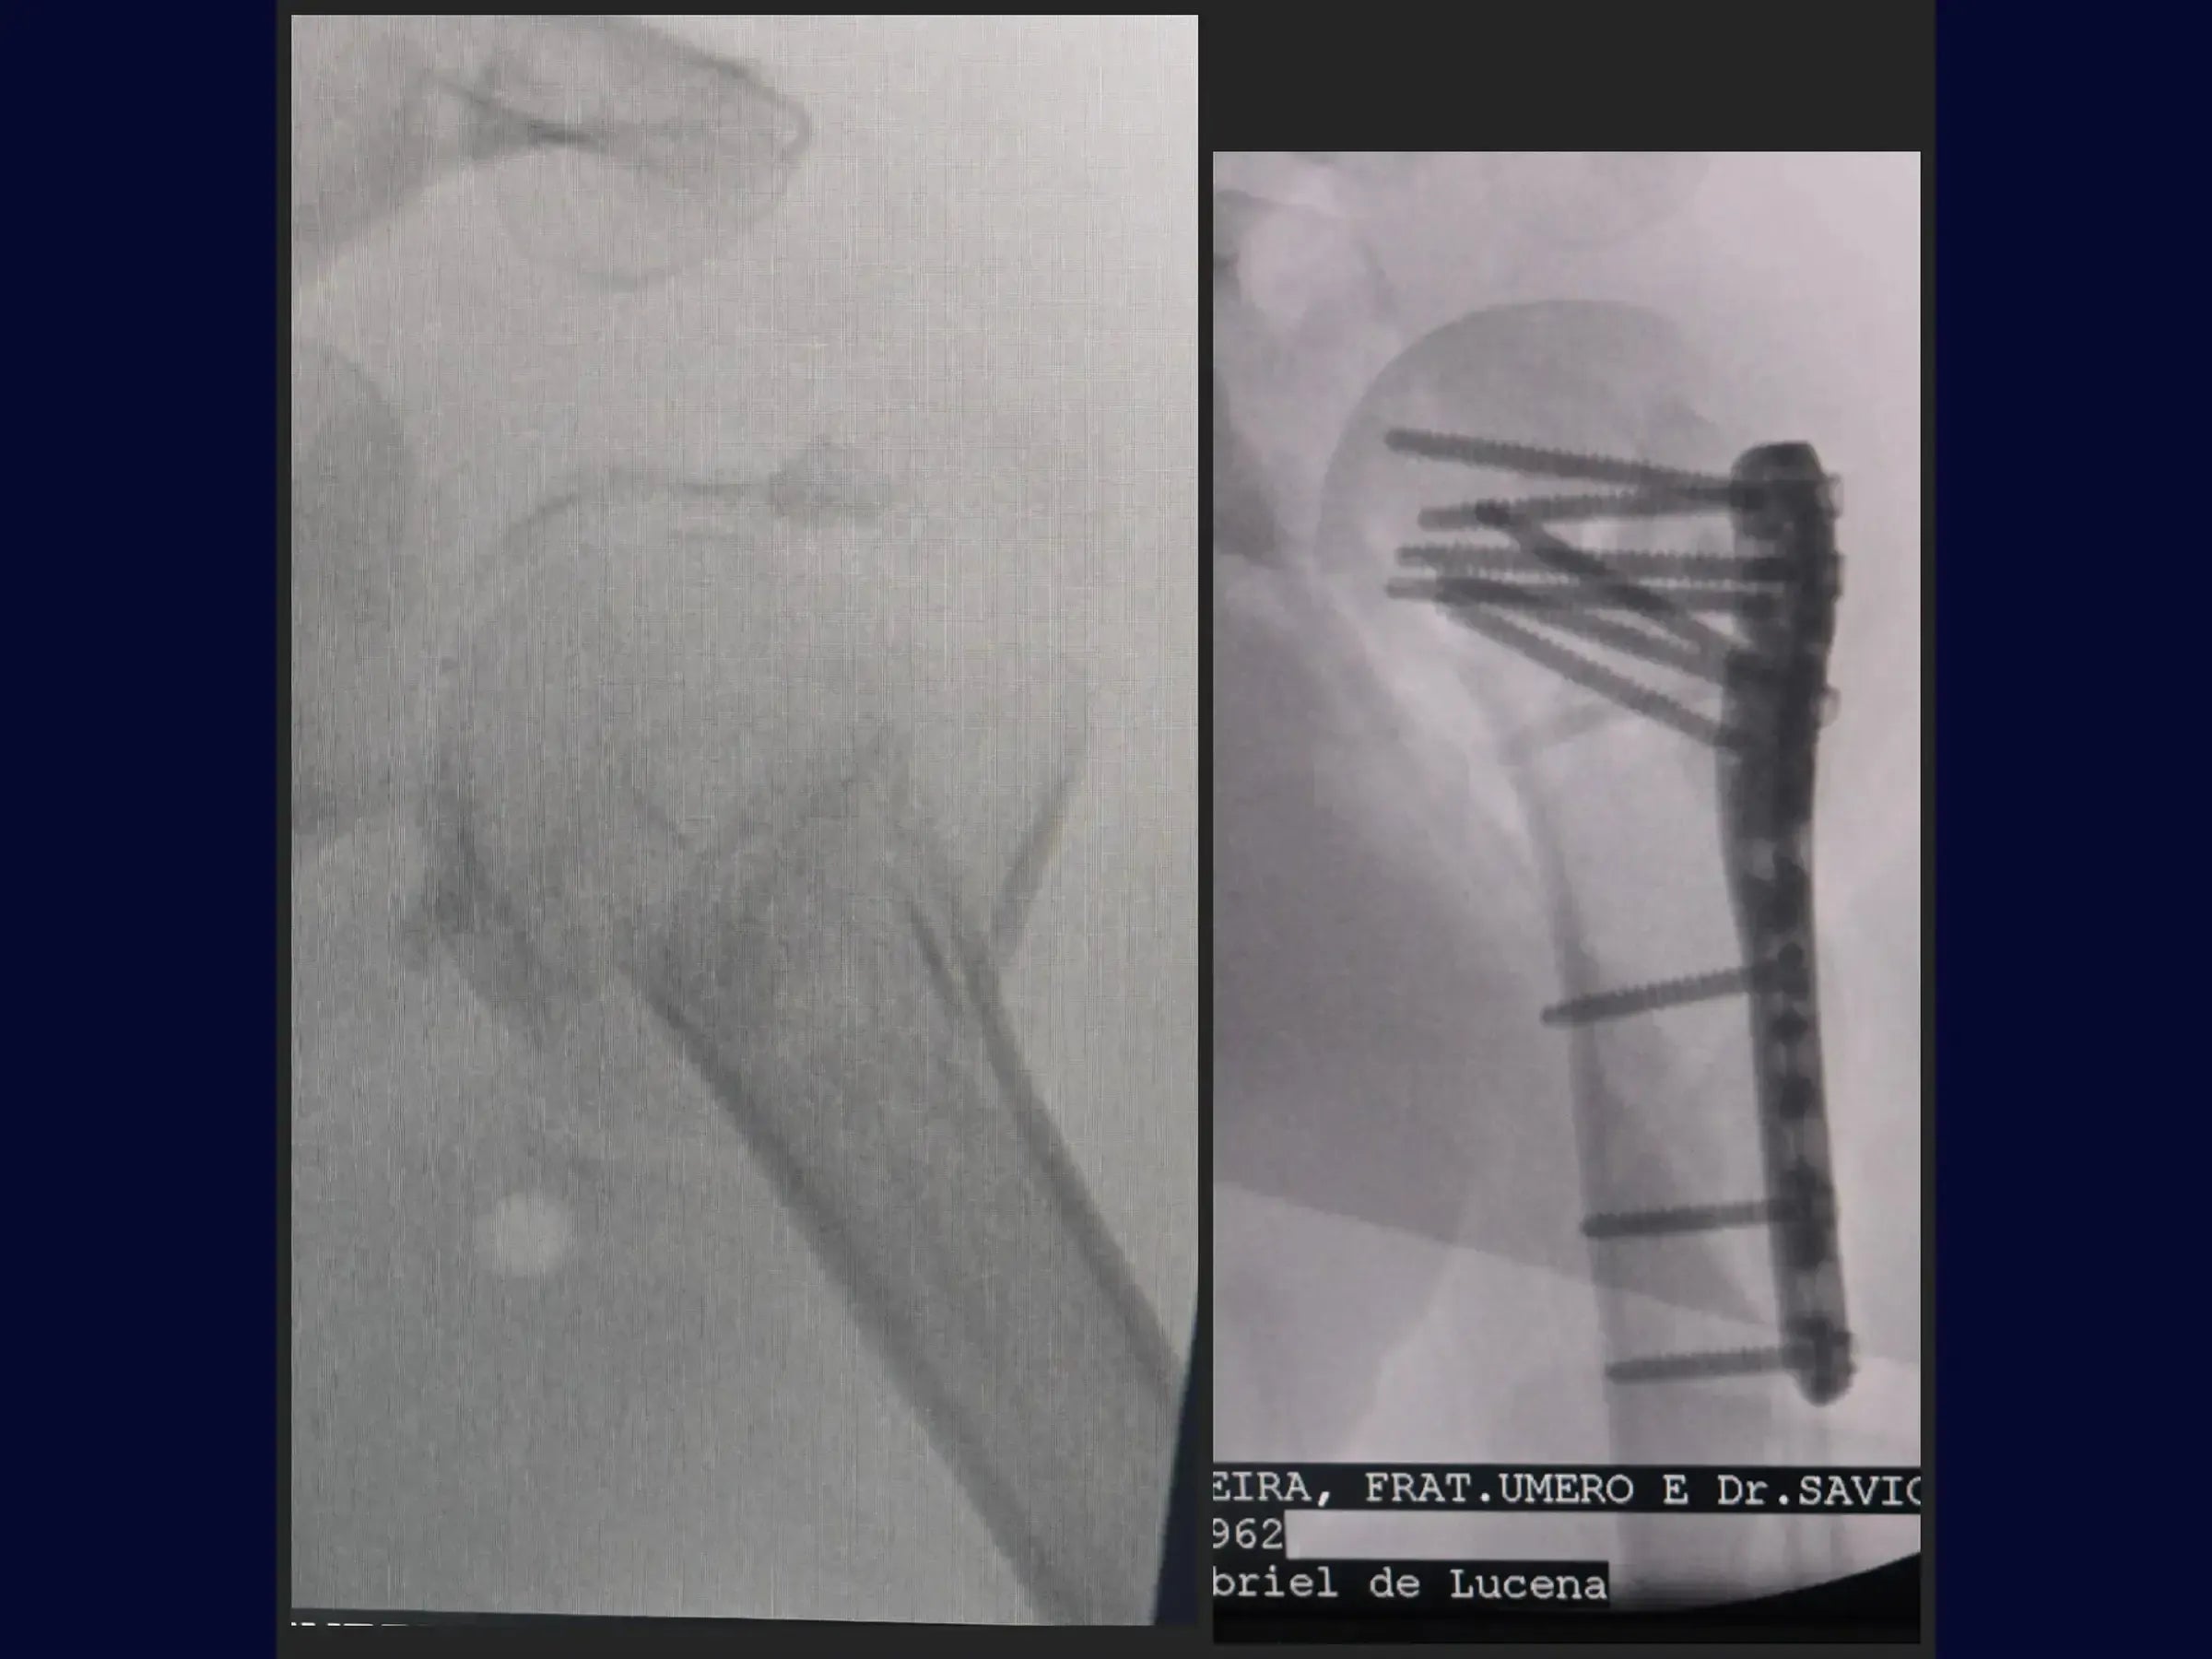

Reconstrução de Fratura Complexa em Quatro Partes do Úmero Proximal

Domine o tratamento de fraturas complexas do úmero proximal. Este treinamento oferece uma imersão técnica na reconstrução de fraturas em quatro partes, com ênfase na abordagem deltopeitoral e fixação com placa e amarrilhas, apresentada em vídeo 4K sob a perspectiva do cirurgião.

- Reconstrução de fraturas complexas em quatro partes do úmero proximal.

- Fixação com placa e amarrilhas.

- Posicionamento e Fixação da Placa: Princípios para posicionamento ideal da placa (1 cm lateral ao sulco bicipital) e inserção de parafusos, incluindo o parafuso dinâmico e parafusos no calcar para estabilidade e alinhamento.